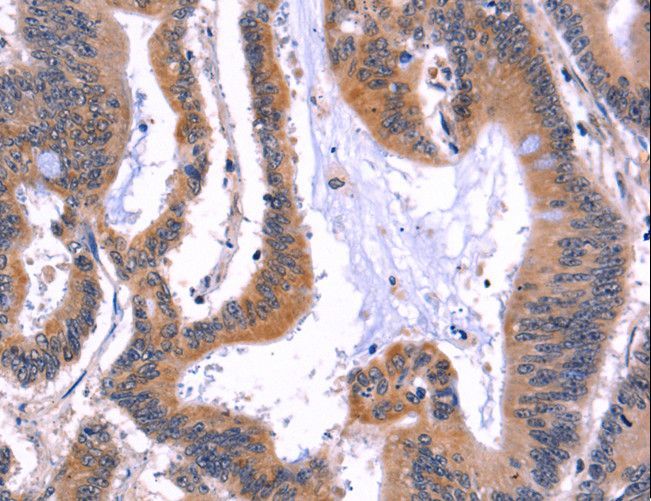

Supportive validation

- Submitted by

- LSBio (provider)

- Main image

- Experimental details

- Immunohistochemistry of paraffin-embedded Human colon cancer using ARC Polyclonal Antibody at dilution of 1:50.